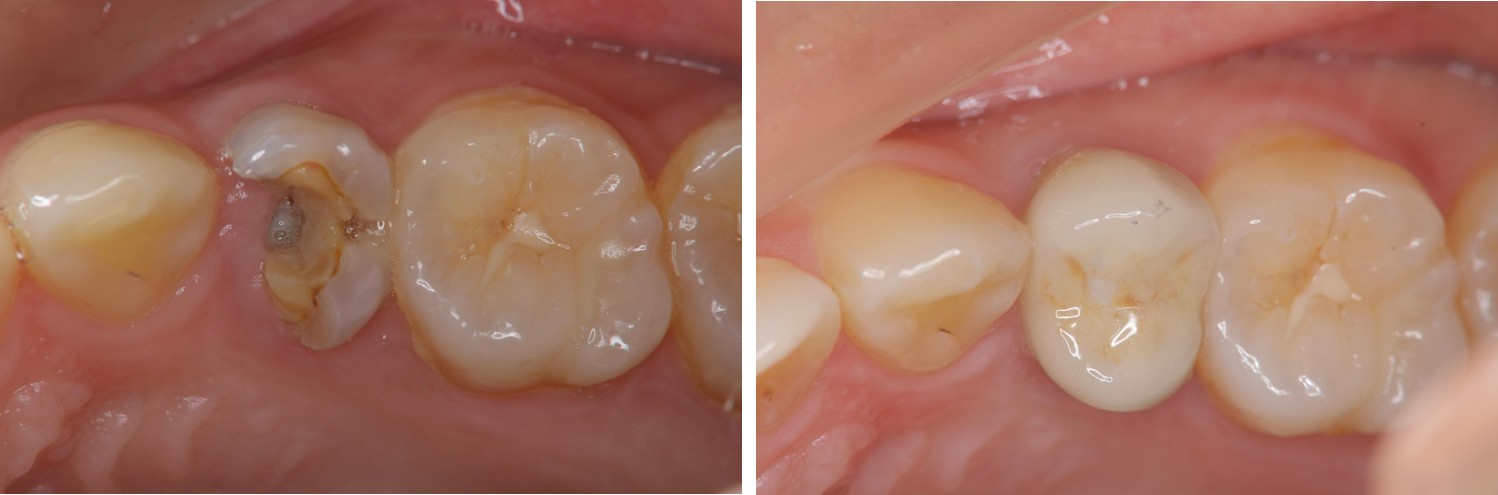

術前、術後比較

治療前,左上小臼齒區二次蛀牙

治療後,牙周咬合良好

治療後,密合度良好